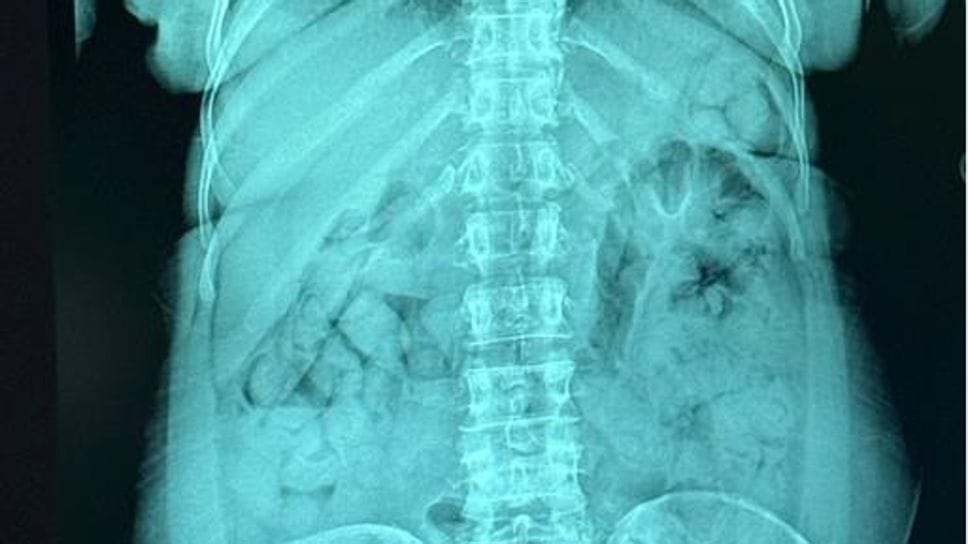

Gli esami e il sequestro

Portata all’ospedale Papa Giovanni XXIII di Bergamo, i radiologi hanno confermato la presenza degli ovuli nello stomaco. Una volta espulsi, sono risultati contenere 1,393 chili di eroina. La sostanza stupefacente è stata sequestrata, mentre la donna è stata arrestata e portata al carcere di Bergamo, a disposizione dell’autorità giudiziaria.